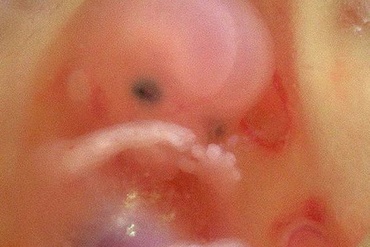

Saptamana 6 de sarcina

Belelusul este in plin proces de organogeneza si creste. Tu esti plina de emotii si stralucesti! Celulele specializate produc nu mai putin de 250.000 de neuroni pe minut!...